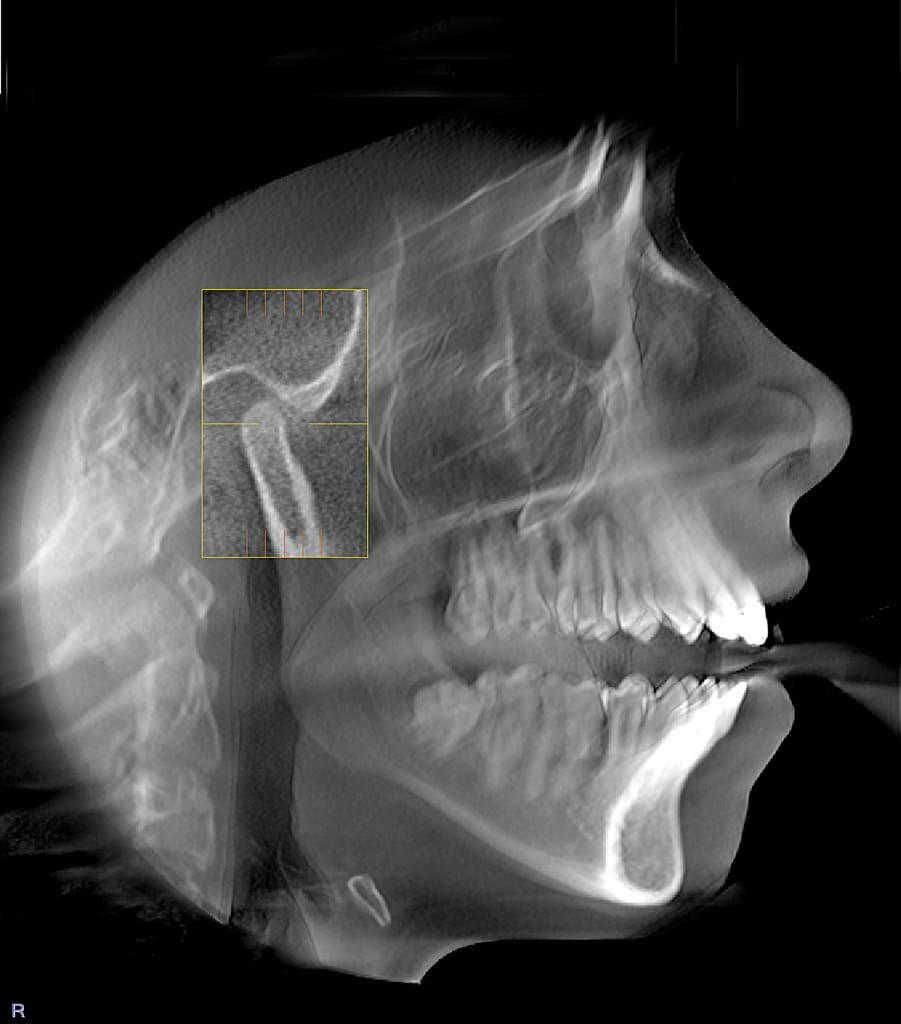

Фотографии ортопантомограмм и работ Родена